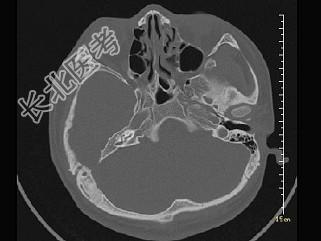

- 单项选择题女,12岁, 自幼右侧听力丧失,CT检查如图, 下列说法错误的是 ( )

A、右侧外耳道闭锁

B、右侧外耳道不发育

C、右侧慢性化脓性中耳炎

D、右侧乳突为板障型

E、应诊断为先天性外耳道畸形